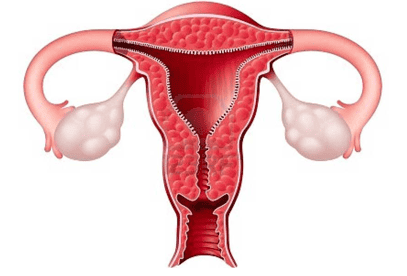

Trong quá trình phẫu thuật lạc nội mạc tử cung, bác sĩ có thể loại bỏ buồng trứng, ống dẫn trứng và tử cung (cắt tử cung) nếu các cơ quan này bị tổn thương và bệnh nhân không có ý định mang thai trong tương lai.

Dù đã phẫu thuật cắt bỏ khối u, tình trạng lạc nội mạc tử cung vẫn có thể tái phát, gây đau đớn cho người bệnh. Khoảng 15% phụ nữ sẽ bị tái phát lạc nội mạc tử cung sau khi đã cắt bỏ hoàn toàn tử cung, cả hai buồng trứng và ống dẫn trứng.

Nếu bệnh nhân được chỉ định cắt bỏ tử cung để điều trị lạc nội mạc tử cung, thời gian hồi phục hoàn toàn sau phẫu thuật sẽ từ 4 đến 6 tuần. Sau khi cắt bỏ tử cung, kinh nguyệt của bệnh nhân sẽ ngừng.